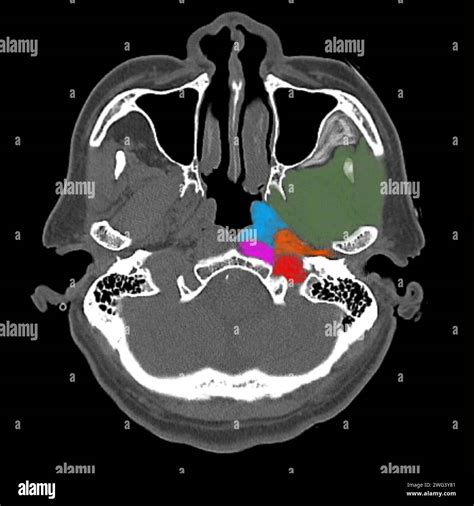

Detailed medical illustration of head and neck anatomy

• head and neck anatomy ct